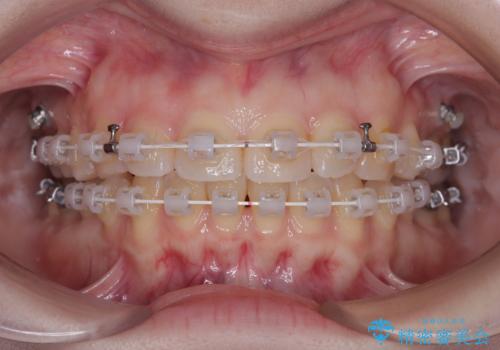

- 審美装置

- 1年4ヶ月

当初はインビザラインを希望されていましたが、職業柄お茶する機会が多く装着時間を確保することが難しいとのことで、相談の上ワイヤー矯正の中では目立ちにくい審美装置で矯正を進めていくこととしました。